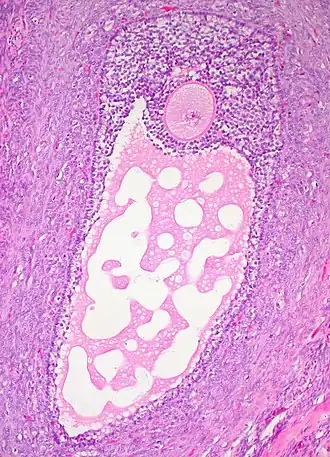

![]() Гистологический срез зрелого фолликула яичника. Ооцит — большая, круглая, розово окрашенная клетка в верхней части изображения. | |

В фолликуле содержится ооцит 1-го порядка. Ядро ооцита называют «зародышевый пузырёк» germinal vesicle (см. иллюстрацию)